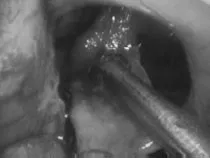

在显微镜、内镜辅助观察下,施罗德教授通过前颞叶开颅手术,成功全切位于视觉神经之间的颅咽管瘤。同时,第三脑室内的肿瘤部分也在神经内镜辅助下切除。

在显微镜下通过终板切除肿瘤

在神经内镜下切除第三脑室内剩余的肿瘤